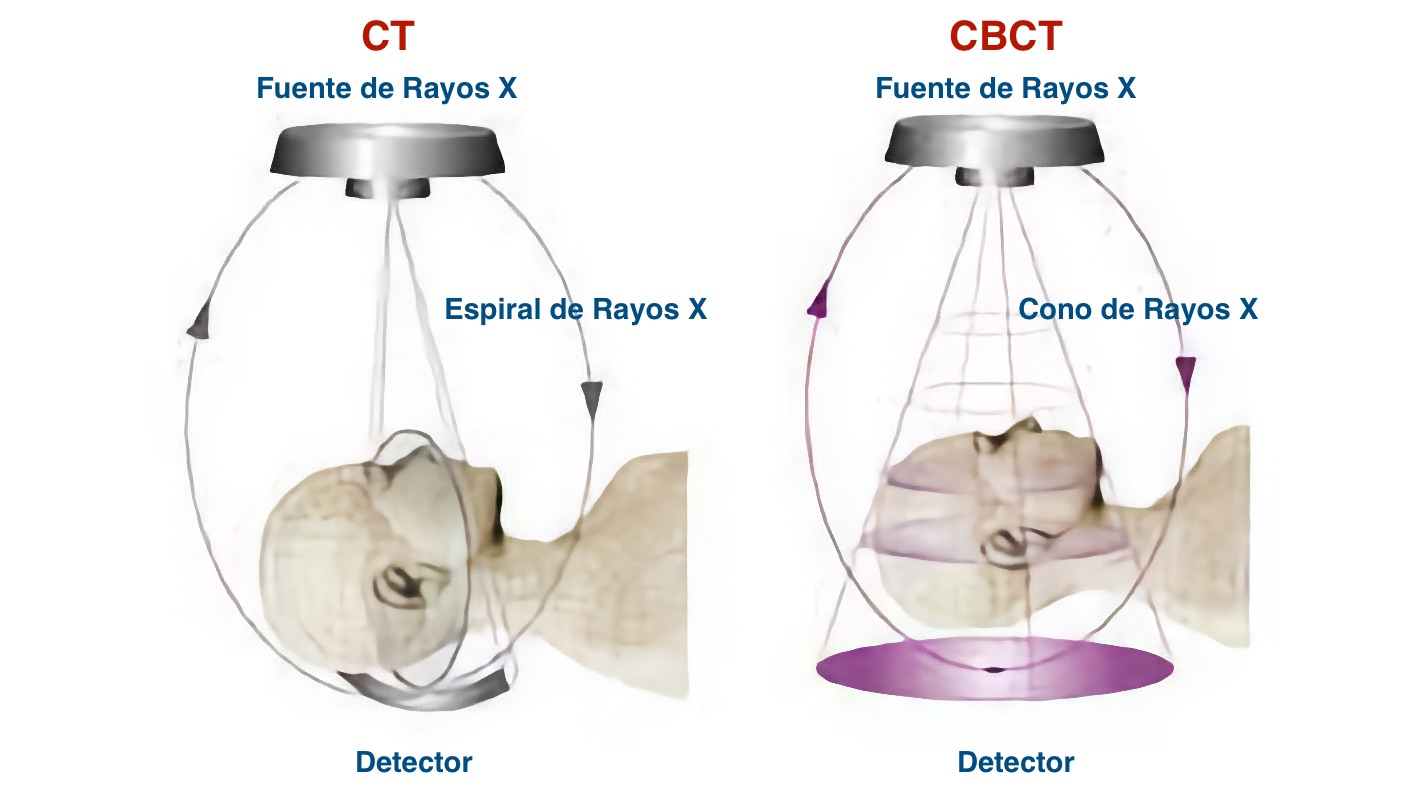

¿Cuál es la diferencia entre tomografía computarizada (TC) y tomografía computarizada de haz cónico (CBCT)?

La tecnología TC fue desarrollada en el año 1967 por Sir Godfrey Hounsfield y se basa en capturar imágenes en las pantallas del detector en múltiples planos hasta obtener una imagen completa, esta técnica requiere de mayor radiación para al paciente. Las imágenes que se obtienen tienen utilidad en traumatismos maxilofaciales, estudios de crecimiento y desarrollo, patología oral y de glándulas salivales y planificación de implantes dentales.

A diferencia de la imagen TC, en la imagen CBCT (Cone Beam Computed Tomography) el volumen tridimensional de los datos es obtenido en un solo barrido de escáner en la que el sensor 2D y la fuente de radiación rotan sincrónicamente alrededor de la cabeza del paciente en 180º o 360º dependiendo del equipo CBCT utilizado.

Además, en un equipo CBCT el haz de rayos X tiene forma cónica y obtiene un volumen de datos cilíndrico o esférico que se conoce como FOV (field of view). El tamaño del FOV difiere en los distintos escáneres, siendo algunos capaces de capturar el esqueleto maxilofacial completo. También algunos equipos CBCT pueden ajustar la altura del FOV cilíndrico para capturar una sola zona, lo que reduce la dosis de radiación al paciente.